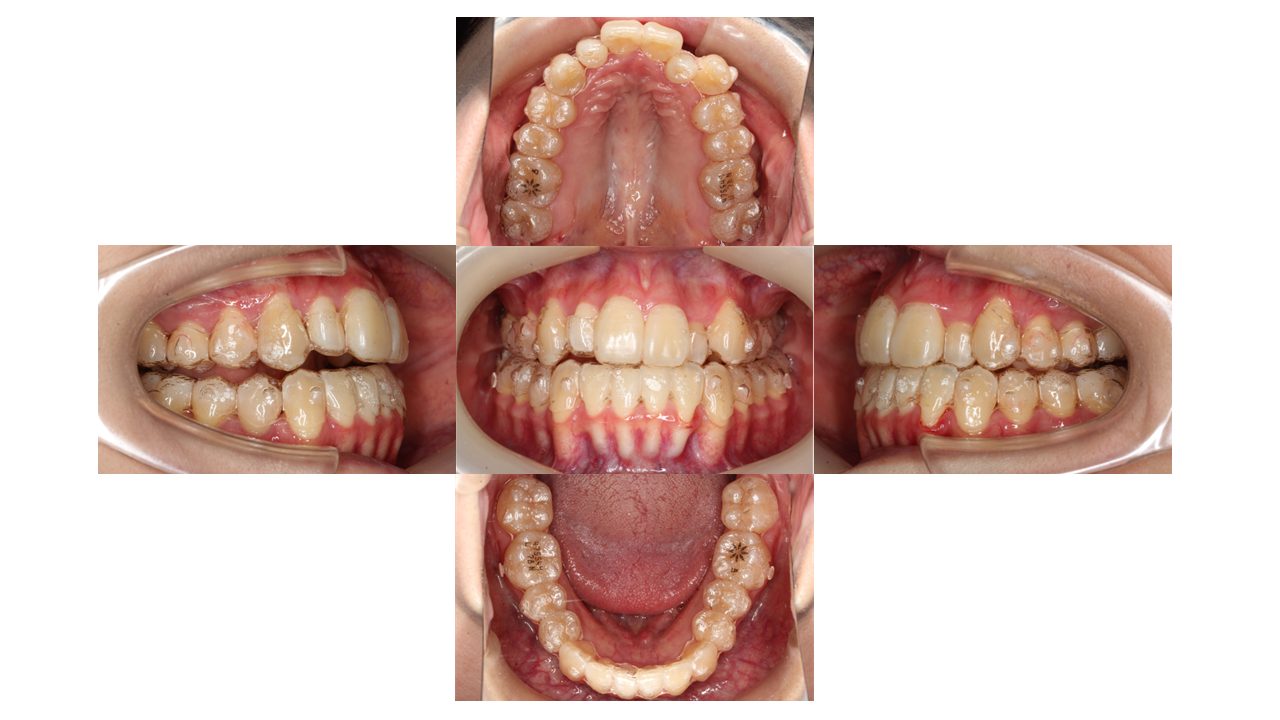

1年7ヶ月経過の口腔内の状態です。

今回は、マウスピースを装着したまま口腔内写真を撮影しています。

少しずつ凸凹が改善してきました。